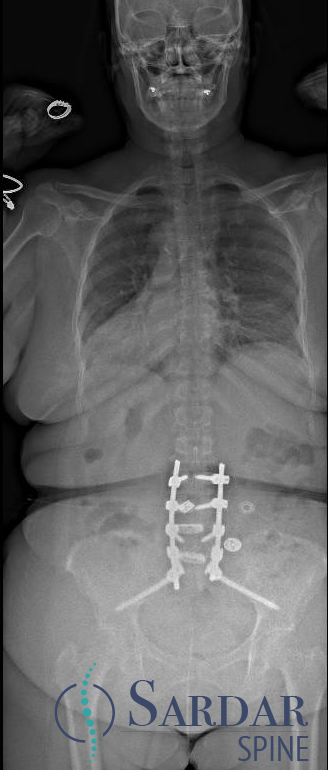

Severe malalignment case: Performed T12-S1/Pelvis posterior instrumentation, TLIF at L5-S1 & L5 PSO. No anterior approach on vascular team's advice. Patient now stands upright & grateful. #SpineSurgery #MedTwitter #scoliosis #flatback #HarringtonRods #ScoliosisWarrior

50s patient with severe malalignment. How would you treat this surgically? Nnee compensation in coronal and sagittal planes. Options: Multisegment instrumentation, TLIF/ALIF/OLIF, PSO, refer to another surgeon? Thoughts? #neurosurgery #spine #scoliosis #flatback #harringtonrods